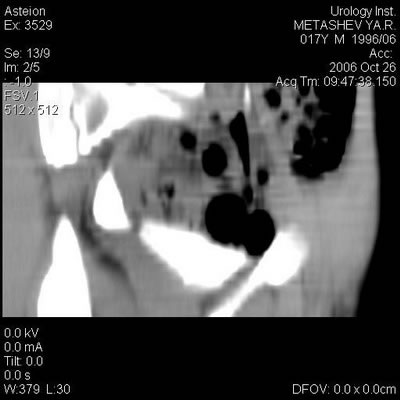

Компьютерная томография

Под эндотрахеальным наркозом произведен разрез по Пфаненштилю,

послойно с поперечным рассечением апоневроза, тупо разведена

прямая мышца живота, выделена и взята на держалки передняя

стенка мочевого пузыря, последняя рассечена поперечно на

протяжении 5-6 см. Устья мочеточников визуализированы в

типичных местах. Поочередно с двух сторон выполнено выделение

устьев мочеточников, мобилизация нижних третей мочеточников

на протяжении 3-4 см. Мочеточники расширены до 15мм в диаметре,

в области интрамуральных отделов определяются их сужения.